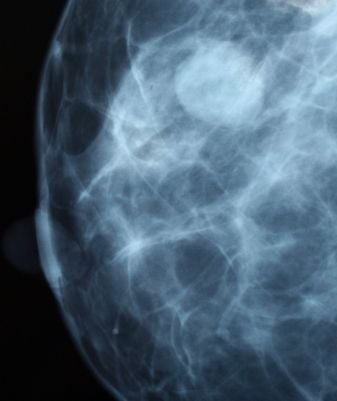

A mellműtét szövődménye: a tokfibrosis

Amikor a szövetek kórosan felszaporodnak az implantátum körül. A folyamat következménye szívós, kemény tapintatú területek kialakulása lehet. Ezek néha csak nagyon kicsinyek, mégis tapinthatók az emlő szövetén át. Kivételes esetekben még az is előfordulhat, hogy az egész emlő elveszíti szokásos rugalmas, lágy tapintatát, és kemény, golyószerű szervvé alakul. Súlyos fibrosis esetén ráadásul valamilyen szokatlan helyzetbe húzódik el az emlő. Erről a lehetőségről már az első megbeszélés során részletes tájékoztatást kell kapniuk a műtétre jelentkező nőknek. A tokfibrosisok ugyanis egyáltalán nem ritkák. Ha valamennyit, az enyhe formákat is figyelembe vesszük, akkor 15-30%-os gyakoriságra kell számítanunk. Rendszerint csak az egyik mellben alakul ki az elváltozás, ritkán fejlődik ki mindkét oldalon. Nagyon fontos tapasztalat, hogy a fibrosis az implantáció utáni első évben már észlelhető szokott lenni. Ilyen esetekben csak egy újabb műtét tud segíteni.Ha azonban a fibrosis csak enyhe, vagyis a mellet csak kissé érezzük keményebbnek, mint normális körülményekközött, akkor egy nagyon egyszerű beavatkozással megoldható a probléma: a sebész a kezével olyan erősen összenyomja a mellet, hogy az emlóben képződött tok szövete elszakad. Ez a módszer kifejezetten fájdalmas és nem is teljesen veszélytelen. A kiterjedtebb, szívósabb fibrosisok esetében azonban műtéti korrekcióra van szükség. A korábbi metszés helyén újra meg kell nyitni a mellet, az implantátumot el kell távolítani, és újat kell betenni a helyére.Sajnos azonban egy újabb implantátum beültetése sem garantálja, hogy nem alakul ki ismét fibrosis. Mindenesetre a korábban említett 30%-os gyakoriság ezekben az esetekben már túlságosan nagy értéknek számít. A betegek ugyanis sokat tehetnek azért, hogy a tokfibrosist elkerüljék. Ha valaki sokat mozog a műtét utáni időben, akkor ezzel a tapasztalatok szerint gyulladás és üregecskék (seroma, pseudocysta) képződését segíti elő, ezekről viszont kiderült, hogy a fibrosis előidézésében oki szerepük lehet. Az orvos által elrendelt nyugalmi periódus betartása tehát nagyon fontos. Különböző vizsgálatok bizonyították, hogy kizárólag a mozgás korlátozásával jelentősen csökkenteni lehetett a fibrosis kifejládésének gyakoriságát. Az új típusú, barázdált, durva felszínű implantátumok bevezetésével sikerült a tokfibrosis kialakulásának gyakoriságát a régebbi 15-30%-ról 2-5%-ra visszaszorítani.